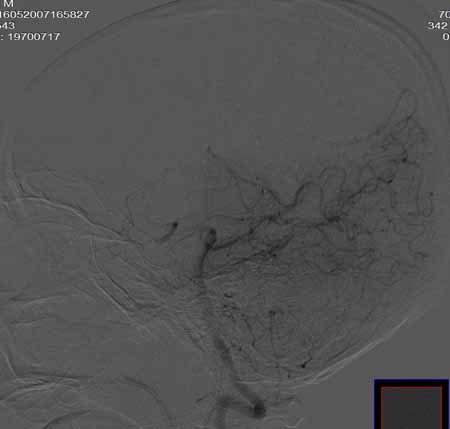

右侧颈总动脉闭塞(血栓形成),左侧大脑前动脉侧支、前交通动脉供应右侧大脑半球

右侧颈总动脉闭塞

右侧颈总动脉闭塞 ,左侧大脑前动脉侧支、前交通动脉供应右侧大脑半球,后交通部分开放 。缓慢代偿血流,分级3

右侧颈总动脉内见充盈缺损,提示血栓/栓子,原因:

1注意有无心房粘液瘤/血栓

2大动脉炎

抗凝治疗

右侧颈总a闭塞,右颈内颈外未显影,左侧未见异常,并通过wills环代偿右侧大脑半球血供